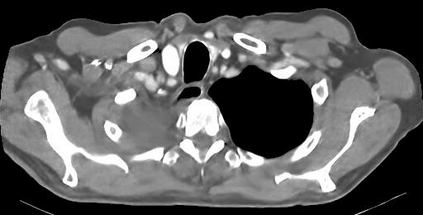

Due to the constraints of the imaging device and high cost in operation time, computer tomography (CT) scans are usually acquired with low intra-slice resolution. Improving the intra-slice resolution is beneficial to the disease diagnosis for both human experts and computer-aided systems. To this end, this paper builds a novel medical slice synthesis to increase the between-slice resolution. Considering that the ground-truth intermediate medical slices are always absent in clinical practice, we introduce the incremental cross-view mutual distillation strategy to accomplish this task in the self-supervised learning manner. Specifically, we model this problem from three different views: slice-wise interpolation from axial view and pixel-wise interpolation from coronal and sagittal views. Under this circumstance, the models learned from different views can distill valuable knowledge to guide the learning processes of each other. We can repeat this process to make the models synthesize intermediate slice data with increasing inter-slice resolution. To demonstrate the effectiveness of the proposed approach, we conduct comprehensive experiments on a large-scale CT dataset. Quantitative and qualitative comparison results show that our method outperforms state-of-the-art algorithms by clear margins.